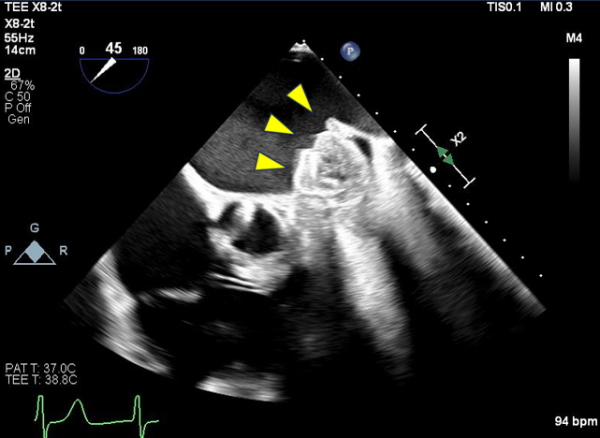

感染性心内膜炎(疣贅と僧帽弁の穿孔)